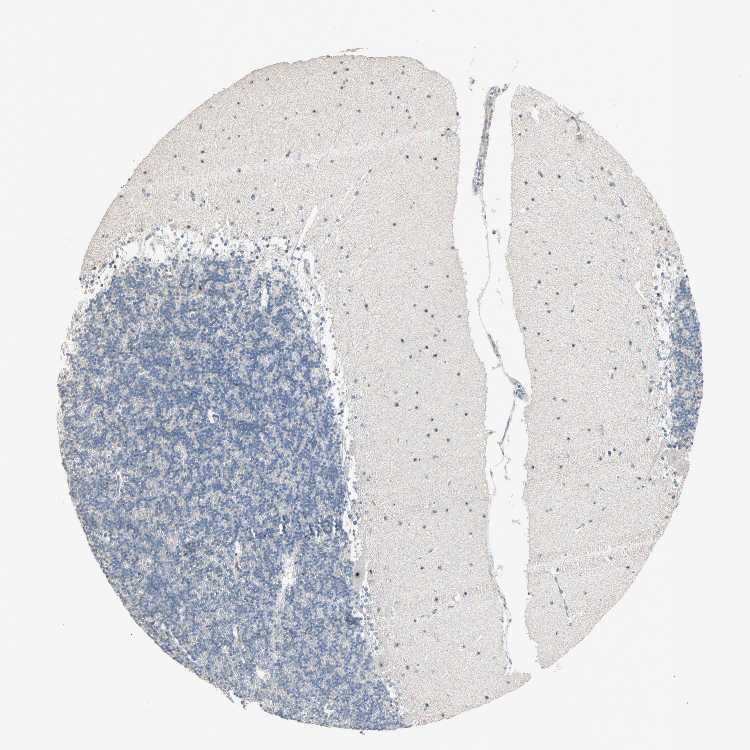

CEREBELLUM - Antibody stainingi

Antibody staining in the annotated cell types in the current human tissue is reported as not detected, low, medium, or high, based on conventional immunohistochemistry profiling in selected tissues. This score is based on the combination of the staining intensity and fraction of stained cells.

Each image is clickable and will lead to virtual microscopy that enables deeper exploration of all samples and also displays staining intensity scores, fraction scores and subcellular localization as well as patient and tissue information for each sample.

Antibody HPA007610

Purkinje cells High

Cells in granular layer Not detected

Cells in molecular layer High